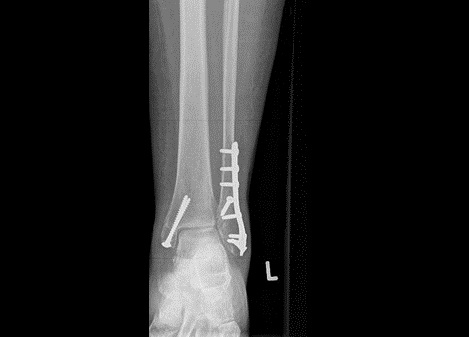

Fig5. - Fracture dislocation of the ankle joint.

Fig5. - Treated with open reduction and internal fixation with plates and screws.